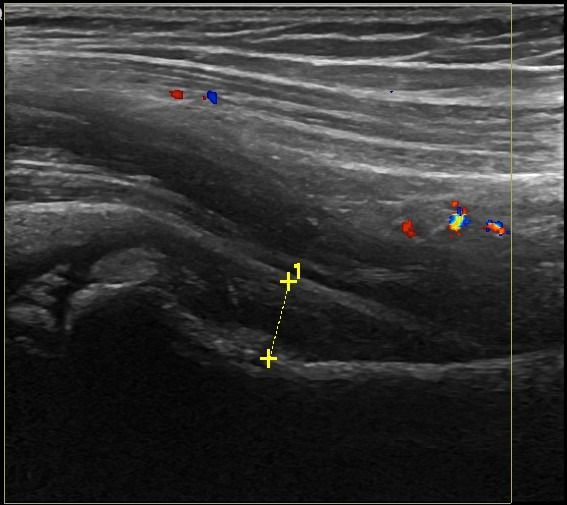

- Συλλογή υγρού

- Τροχαντηρίτιδα: συλλογή υγρού στους θυλάκους των γλουτιαίων τενόντων στο μείζονα τροχαντήρα

- Θυλακίτιδα: Συλλογή υγρού στο θύλακο του τένοντα του Λαγονοψοΐτη